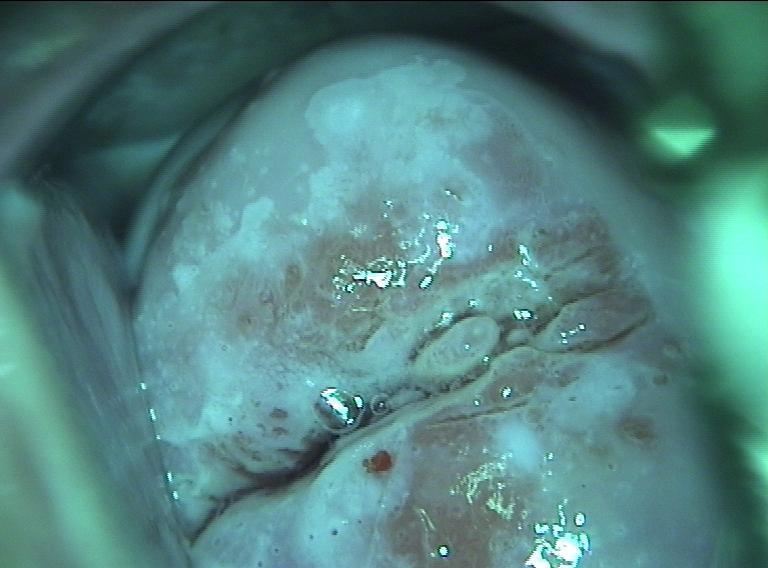

After the cervix is studied with the colposcope, the cervix is washed with a chemical called 3 – 5% acetic acid. The acetic acid dissolves mucus and stains the abnormal areas white. (acetowhite lesions). Staining with a dilute iodine solution (known as Lugol's solution or Schiller's solution) is also performed to further examine for abnormalities. Normal cells will generally take up the iodine stain (and turn brown) in a uniform manner, whereas severe precancerous and cancerous areas will not.

Color filters help the physician examine tiny blood vessels (capillaries) in the area of the squamocolumnar junction. Blue or green filtered light can cause abnormal capillaries to become more obvious, usually inside an acetowhite area. Normal capillaries are slender and spaced out evenly. In contrast, abnormal capillaries can appear as red spots (thickened capillaries seen on end) or can produce a pattern resembling hexagonal floor tiles.

Colposcopy allows tissue sampling (biopsy) that is targeted to the abnormal areas. In fact, the biopsy of abnormal areas is a critical part of colposcopy because treatment will depend on how severe the abnormality is on the biopsy sample.

If the biopsy results show pre-cancer (dysplasia) or cancer, treatment is recommended. The dysplasia may be mild, moderate, or severe. Almost all women with dysplasia can have their treatment procedures performed in the doctor's office. The physician chooses between two general types of treatment. The first type is destruction (ablation) of the abnormal area, and the second type is removal (resection). Both types of treatment cure 90% of patients with dysplasia, meaning that 10% of women will have a recurrence of their abnormality after treatment. Generally, destruction (ablation) procedures are used for milder dysplasia and removal (resection) is recommended for more severe dysplasia or cancer.